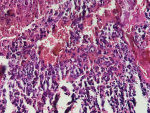

Diagnostic assessment: magnetic resonance imaging of the brain demonstrated an infiltrative thalamo-peduncular lesion with hyperintensity on T2/FLAIR sequences and faint enhancement on post-contrast T1, raising concern for an infiltrative high-grade glioma and creating diagnostic uncertainty (Figure 1, Figure 2). A stereotactic biopsy was subsequently performed. Initial histological evaluation suggested a high-grade glioma; however, immunohistochemical staining revealed strong positivity for CD117, PLAP, and OCT4, findings consistent with a pure germinoma (Figure 3, Figure 4). Staging with thoraco-abdominopelvic CT identified nonspecific pulmonary micronodules (Figure 5), while serum tumor markers remained within normal limits (Table 1). As shown above, the patient's LDH level is elevated compared to the reference range, while both β-HCG and α-FP are within normal limits. These values are important for the diagnostic evaluation and ongoing management of intracranial germ cell tumors.

Figure 3: histopathological appearance of the tumor on hematoxylin-eosin staining: hematoxylin-eosin stained section showing a population of tumor cells with round hyperchromatic nuclei arranged in diffuse sheets (original magnification x20)

Figure 4: immunohistochemical nuclear staining of tumor cells supporting germinoma: immunohistochemical staining showing strong nuclear positivity of tumor cells for OCT4, consistent with the diagnosis of germinoma